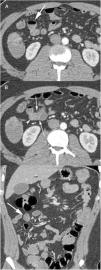

The presence of an MD in a MDCT should be suspected when a blind tubular structure connected to the terminal ileum by a neck of variable size is observed. Multiplanar 2D reconstructions images and CT enterography can help in the diagnosis. In patients with symptoms of obstruction or intestinal inflammation, the possibility of a complication secondary to a MD should be considered, especially when the terminal ileum and the vermiform appendix are normal. MDCT angiography, in cases of acute gastrointestinal bleeding, can identify contrast extravasation and accumulation of blood in the MD, and could demonstrate the persistent omphalomesenteric artery, which is diagnostic of MD. Other MDCT findings such as the presence of enteroliths or associated inflammatory changes around the MD can facilitate the preoperative diagnosis of MD complications.